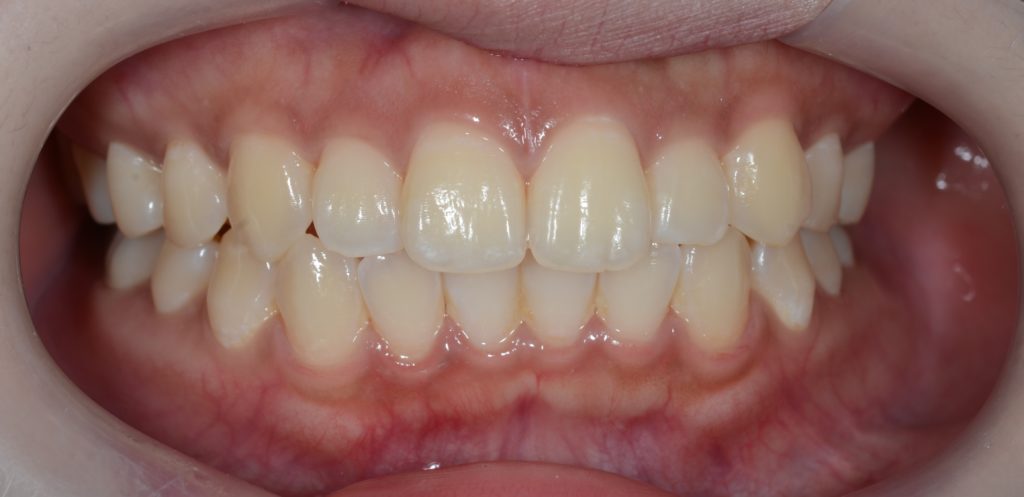

【Before】

【After】

左側が矯正治療前、右側が矯正治療後

オトガイ部にあった梅干し状のシワがほぼ無くなったことが分かります。

矯正後は口元がとてもスッキリしたことが見て取れると思います。